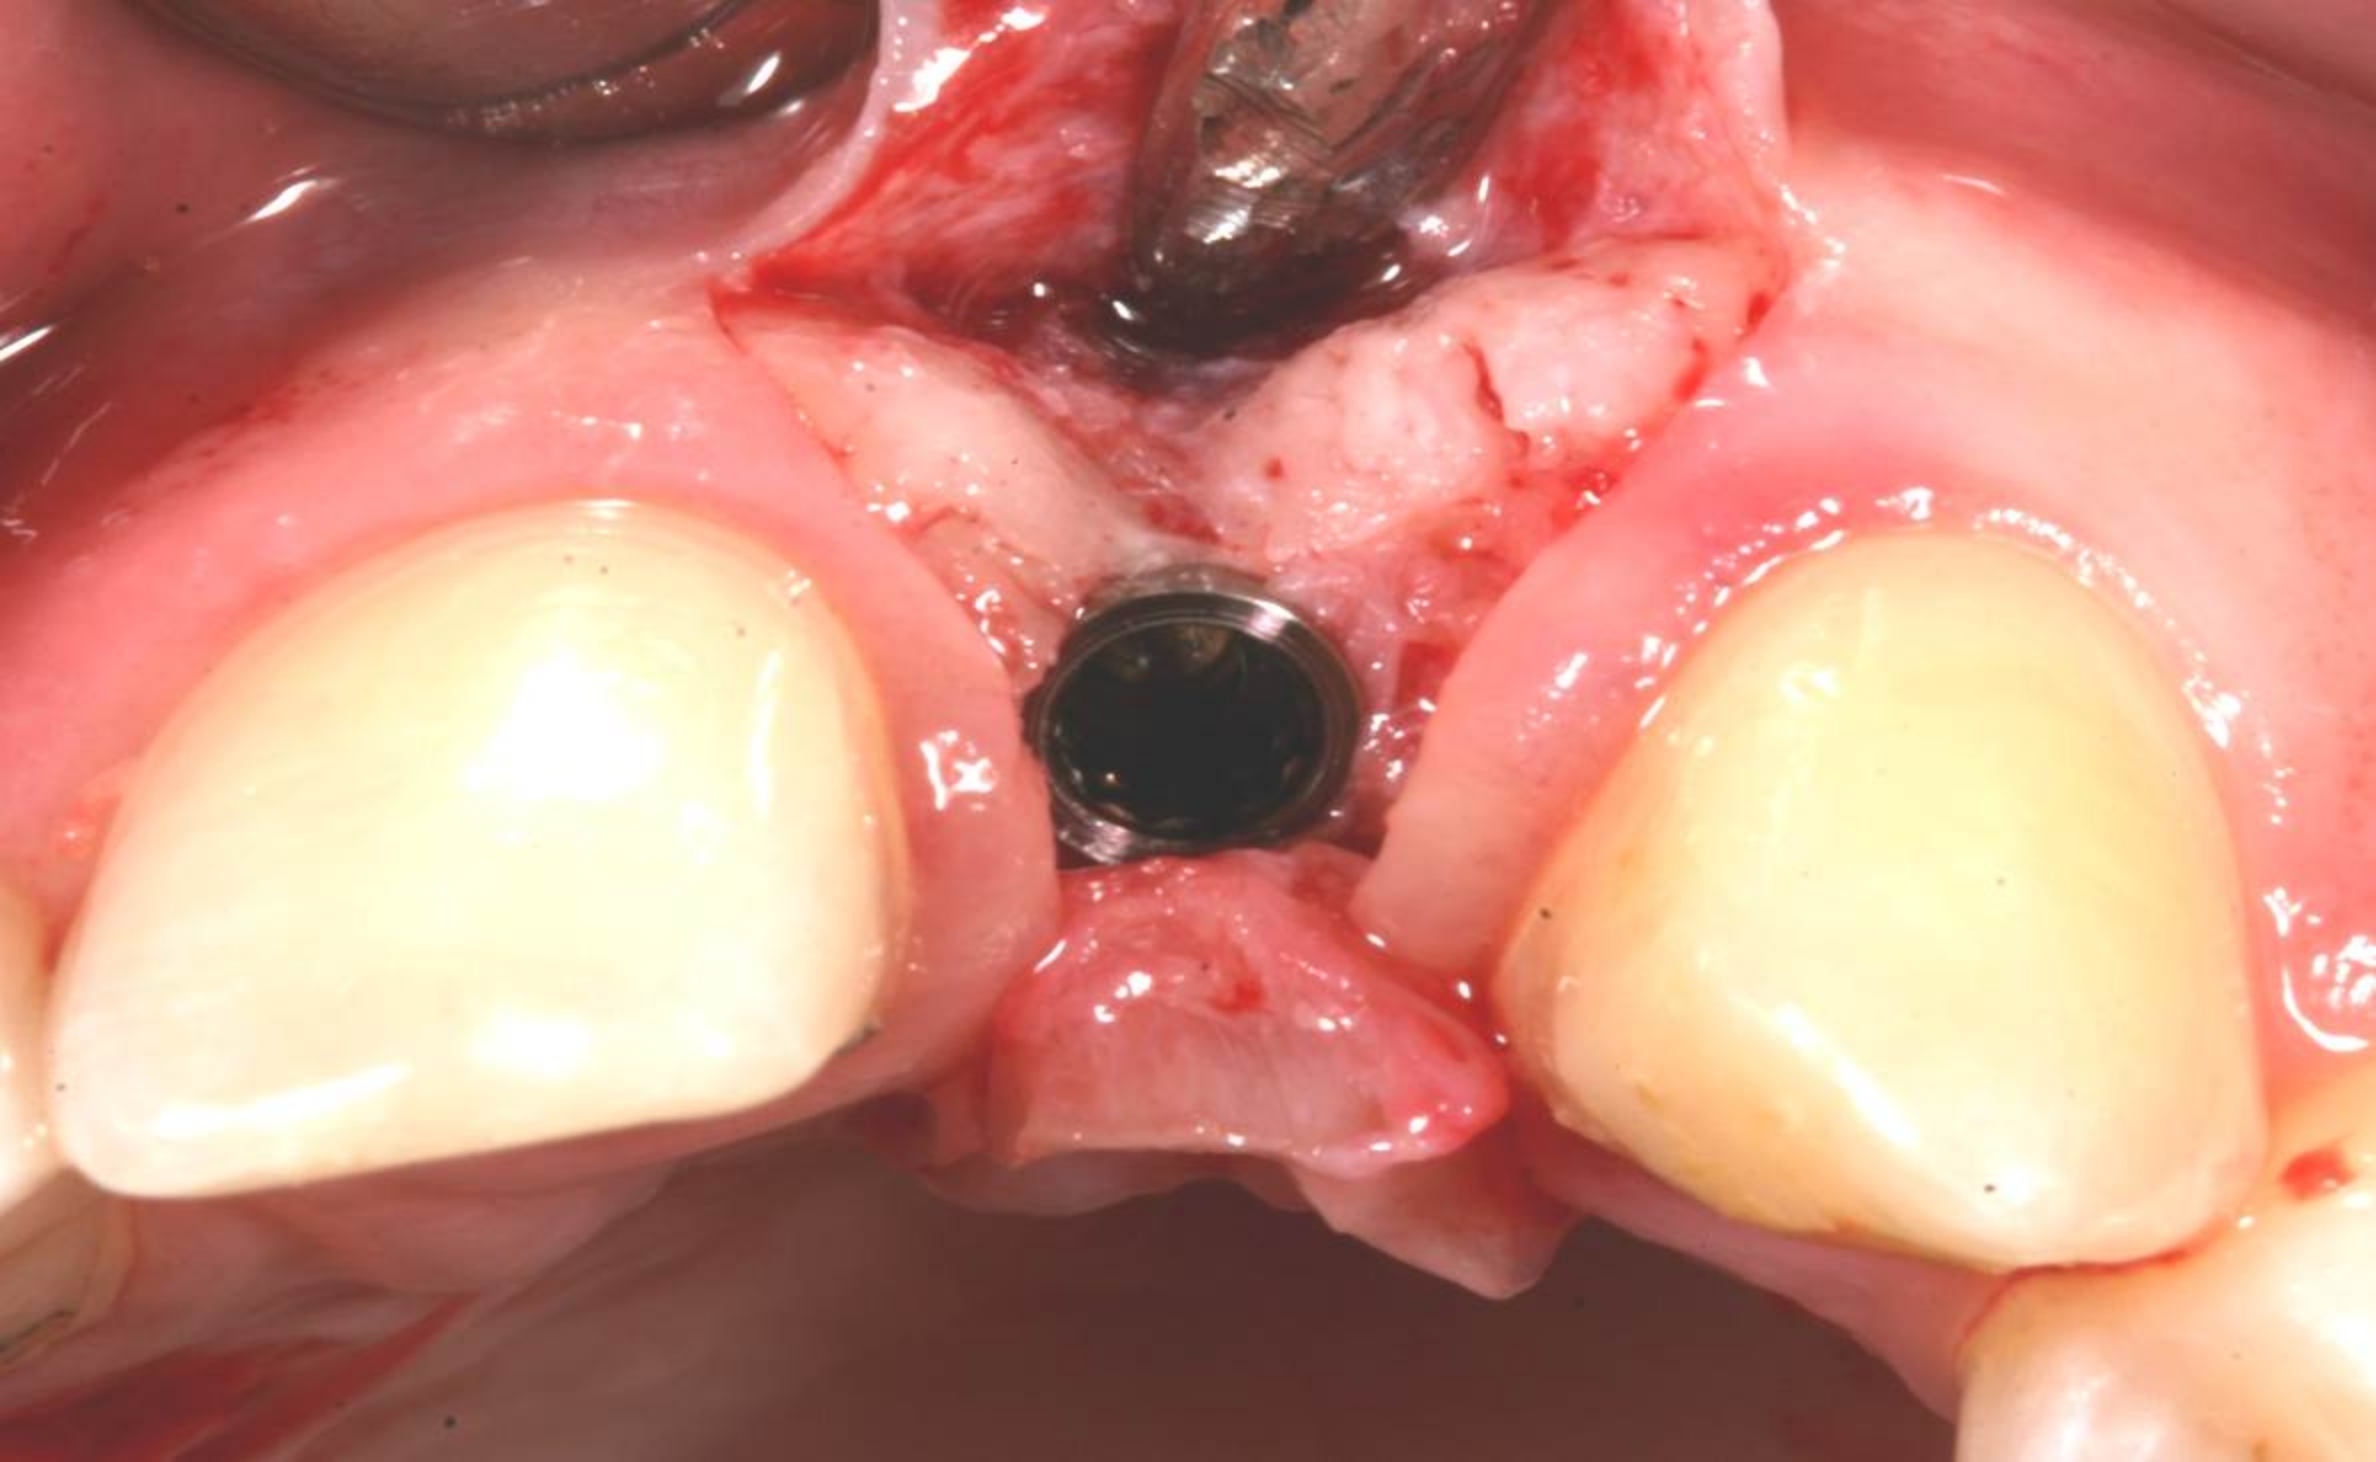

Case 3: Congenitally missing lateral incisors at the sites of teeth Nos. 7 and 10. Both sites were treated simultaneously. (Treatment at the site of tooth No. 10 is illustrated.)

Figure 19

Fig 20. Papillae-sparing incisions were developed both horizontally and vertically. The pedicle flap was elevated, exposing a thin ridge.

Figure 20